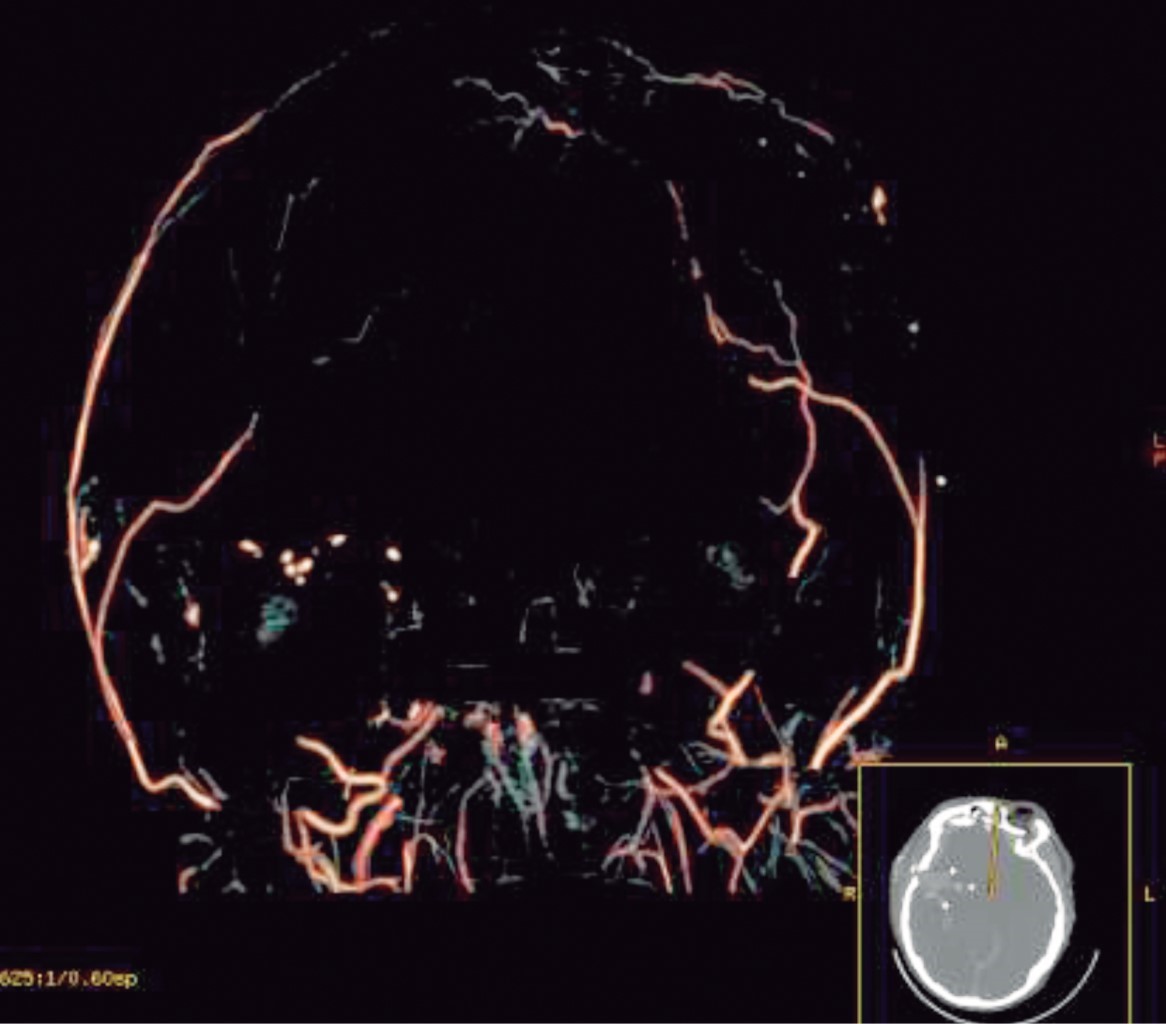

Se presenta el caso de masculino de 16 años de edad que ingresa con diagnóstico de herida por arma de fuego en cráneo, para su evaluación por el Servicio de Neurocirugía, quien establece la muerte encefálica por clínica corroborada por estudio de angiotomografía (Figura 1), donde se aprecia ausencia de flujo arterial cerebral, avisando a la Coordinación de Donación de Órganos y Tejidos con fines de trasplante. Sin antecedentes de importancia, síntomas ni vacunación previa para COVID-19. Se aborda a familiares para solicitar la donación de órganos; la madre, ya que un año previo había fallecido el padre, acepta que se inicie el proceso. Se realizó protocolo de ingreso con laboratorios (Tabla 1) y estudios de gabinete, además de colocación de catéter venoso central; se realiza telerradiografía de tórax sin evidencia que sugiera lesiones o patología pulmonar (Figura 2). La prueba de reacción en cadena de la polimerasa con transcriptasa inversa (PCR-RT) para SARS-CoV-2 se realizó vía nasofaríngea y se envió al Laboratorio Estatal de Salud Pública de nuestro estado quien realiza el procesamiento de estas muestras. Al mismo tiempo se realizaron estudios de laboratorio para evaluar los órganos y tejidos viables para trasplantes siendo el corazón, hígado, ambos riñones, ambas córneas y tejido musculoesquelético. Sin embargo, al ser donante pediátrico grupo y Rh sanguíneo B+, se contactó al Centro Nacional de Trasplantes (CENATRA) para la búsqueda de receptores, cabe mencionar que no hubo receptores para el órgano cardiaco. Un centro hospitalario refirió tener receptor de hígado con urgencia de trasplante, dos centros refirieron tener un receptor pediátrico cada uno para los riñones, otro centro aceptó tener receptores de córneas y un banco de tejidos aceptó participar en la extracción del tejido musculoesquelético.

Figura 1